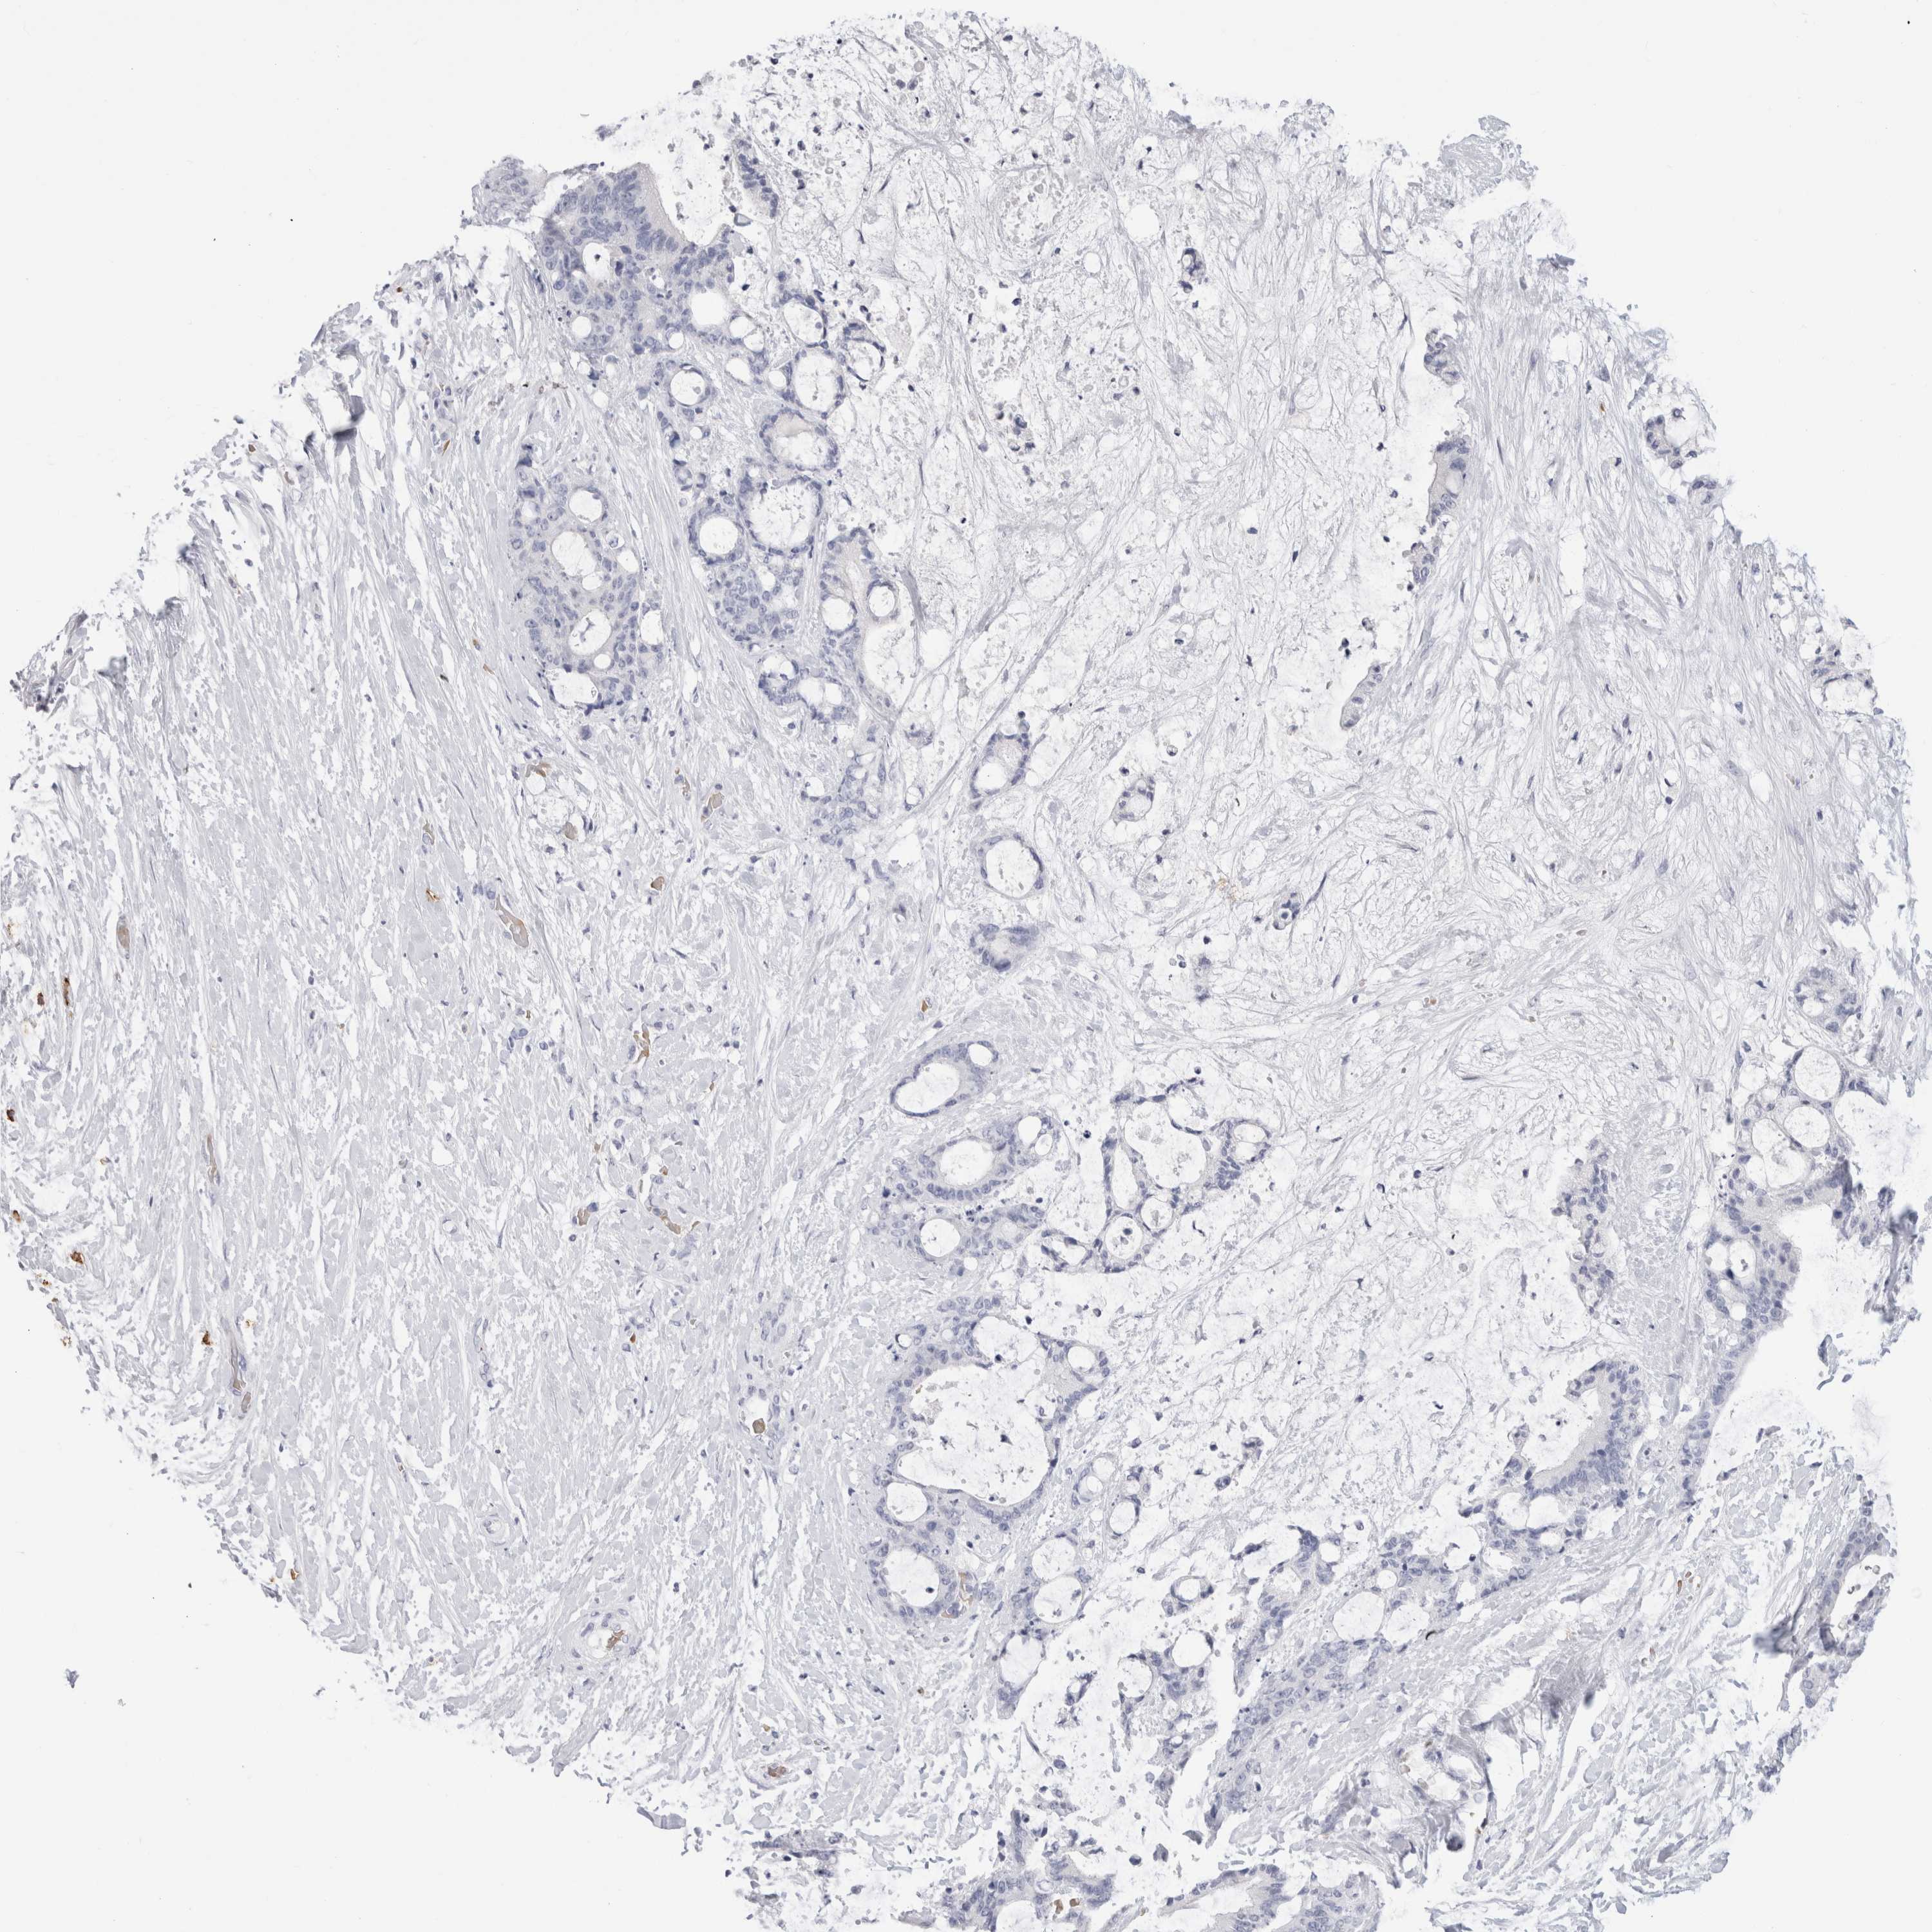

LIVER CANCER - Protein expressioni

A mouse-over function shows sample information and annotation data. Click on an image to view it in a full screen mode. Samples can be filtered based on level of antibody staining by selecting one or several of the following categories: high, medium, low and not detected. The assay and annotation is described here.

Note that samples used for immunohistochemistry by the Human Protein Atlas do not correspond to samples in the TCGA dataset.

Antibody stainingi

Antibody staining in the annotated cell types in the current human tissue is reported as not detected, low, medium, or high, based on conventional immunohistochemistry profiling in selected tissues. This score is based on the combination of the staining intensity and fraction of stained cells.

Each image is clickable and will lead to virtual microscopy that enables deeper exploration of all samples and also displays staining intensity scores, fraction scores and subcellular localization as well as patient and tissue information for each sample.

Antibody HPA022132

Antibody HPA052381

Antibody CAB002493

Antibody CAB025255

Staining

High

Medium

Low

Not detected

Intensity

Strong

Moderate

Weak

Negative

Quantity

>75%

75%-25%

<25%

None

Location

Nuclear

Cytoplasmic/membranous

Cytoplasmic/membranous,nuclear

Cholangiocarcinoma

Carcinoma, Hepatocellular, NOS